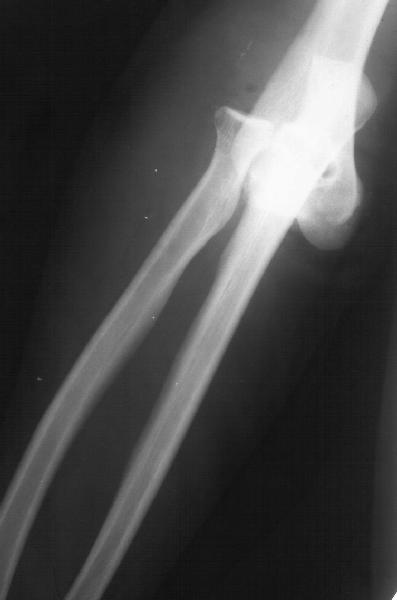

Yesterday (3 weeks post reduction) the plaster was removed to start motions. Gross elbow instability was revealed - the forearm easily can be displaced medially, and reduced back. Recent films with and without subluxation also attached.

What to do? Continue plaster for some more weeks? Revision and repair of medial collateral ligament? XF with hinges? Today the elbow ROM is about 60/150 (with 180 as full extension).